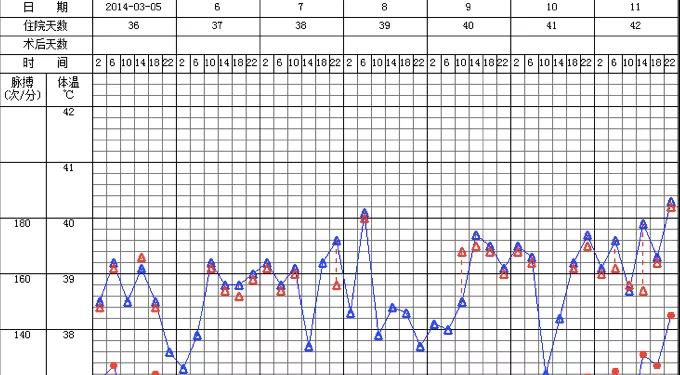

当时癫痫原因考虑感染中毒性脑病可能,不除外脑外伤后遗症。后患者持续高热,体温波动在39~40℃之间(图8)。

图8. 3月5-11日体温变化曲线